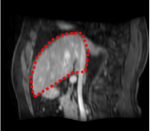

An example of CT/CBCT and MR/CBCT registration results are shown in figures 3 and 4, respectively. For both cases, the CBCT image (first column) was acquired intra-operatively after needle insertions and was employed as a reference for image registration. The pre-operative image is displayed before registration (second column), after PM-EA (third column) and after PM-EA+Evo (fourth column). The occurrence of patch shifts is reported for each spatial direction in panels (m–o): for each histogram, the shift with maximal occurrence is shown by the red dashed line. For panels (a–l), a ROI — manually defined on the CBCT image/encompassing the liver — is shown using red dash lines. Our visualization shows an improved correspondence of the contour of the liver with the manually defined liver boundary when the PM-EA solution is employed (see 3(c,g,k) and 4(c,g,k)). Moreover, an even better correspondence of the contour is observable using the PM-EA+Evo solution (see 3(d,h,l) and 4(d,h,l)).

Trans.

[X-Y]

CBCT

(a)

CT / No registration

(b)

CT / PM-EA

(c)

CT / PM-EA+Evo

(d)

Sag.

[X-Z]

(e)

(f)

(g)

(h)

Cor.

[Y-Z]

(i)

(j)

(k)

(l)

(m)

(n)

(o)